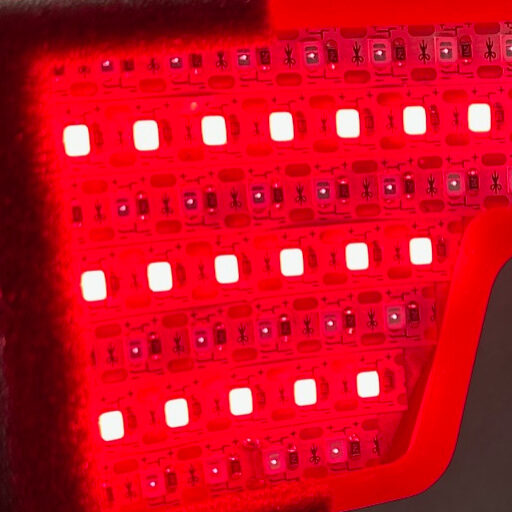

LLLT was conducted on patients at Dankook University Hospital upon the scheduled visits of each patient. Light irradiation was performed with a LED-based array matrix module with 5 planar panels. For the first 1 min of irradiation a wavelength of 590 nm in continuous wave and an irradiance of ≈ 50 µW/cm² scanned panel by panel for 1 s per panel, giving a fluence of ≈ 50 µJ/cm². At the end of that minute, 830 nm was delivered from all 5 panels at an irradiance of 100 mW/cm² for 10 min in continuous wave mode. The energy density over the entire near field area (encompassing the entire face and orbital area) was therefore ≈ 60 J/cm² per session.